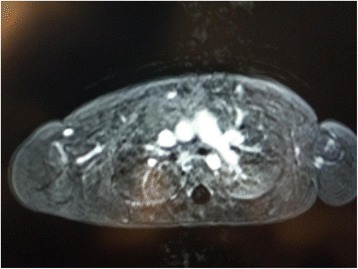

A two-day-old female infant, born at term after uneventful pregnancy, was referred to our paediatric cardiology team to be evaluated for a light murmur. She was born by vaginal delivery; her post-natal adaptation was normal and auxometric parameters were adequate for her gestational age. No clinical signs of dysmorphism or cyanosis or dyspnea were evident; her peripheral oxygen saturation was 98% at room air and the heart rate was normal. On cardiac auscultation, a 1-2/VI murmur could be heard in the left upper sternal border; pulmonary auscultation as well as peripheral pulses were normal. Colour-Doppler echocardiography revealed the absence of the right pulmonary artery, whereas the main and left pulmonary arteries had normal size. The pulmonary valve was normal. There was no evidence of a patent ductus arteriosus (PDA) nor other cardiac defects except for a small patent foramen ovale. The size and function of both cardiac ventricles were normal and without ventricular hypertrophy. The size and origin of the coronary arteries, as well as the aortic arch, were normal. A physiological tricuspid insufficiency was noticed, with an estimated pulmonary artery pressure of 30 mmHg. These cardiovascular features were confirmed by echocardiographic examination, 1 week later. Suspecting an isolated unilateral absence of the right pulmonary artery (UARPA), we decided to carry out chest X-ray and MRI. The former showed normal pulmonary aeration with regular size of both lungs and a normal cardiac silhouette, the latter showed the absence of the right pulmonary artery, with a slightly increased lumen and size of the main and left pulmonary arteries (Fig. 1). Fortunately, the right lung was shown to be perfused by some systemic collateral arteries arising principally from the right subclavian artery and from the celiac trunk. MRI also excluded other heart defects and confirmed normal cardiac function.

Fig. 1.

Chest MRI, at one month of age, showing isolated unilateral absence of the right pulmonary artery

In our patient, chest MRI, performed 1 month after birth, confirmed the absence of the right pulmonary artery. Moreover, the right lung was shown to be perfused by some systemic collateral arteries arising principally from the right subclavian artery and from the celiac trunk, in the absence of any other malformation. MRI also excluded other cardiac anomalies, confirming an isolated UARPA. In some cases of UAPA chest radiography and MRI may evidence some anomalies such as ipsilateral small hemithorax, mediastinal e tracheal shift toward the affected side, ipsilateral hemi-diaphragm elevation, ipsilateral diminished pulmonary vascular markings and contralateral lung hyperinflation [14]. We recommend chest MRI to confirm the diagnosis of isolated UAPA and to identify the collateral arteries supplying the affected lung.